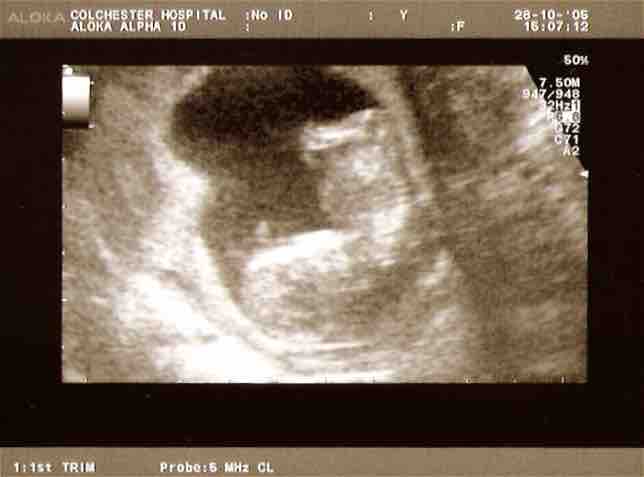

Ultrasound scan

Ultrasound is used to monitor the age and health of the fetus during pregnancy.